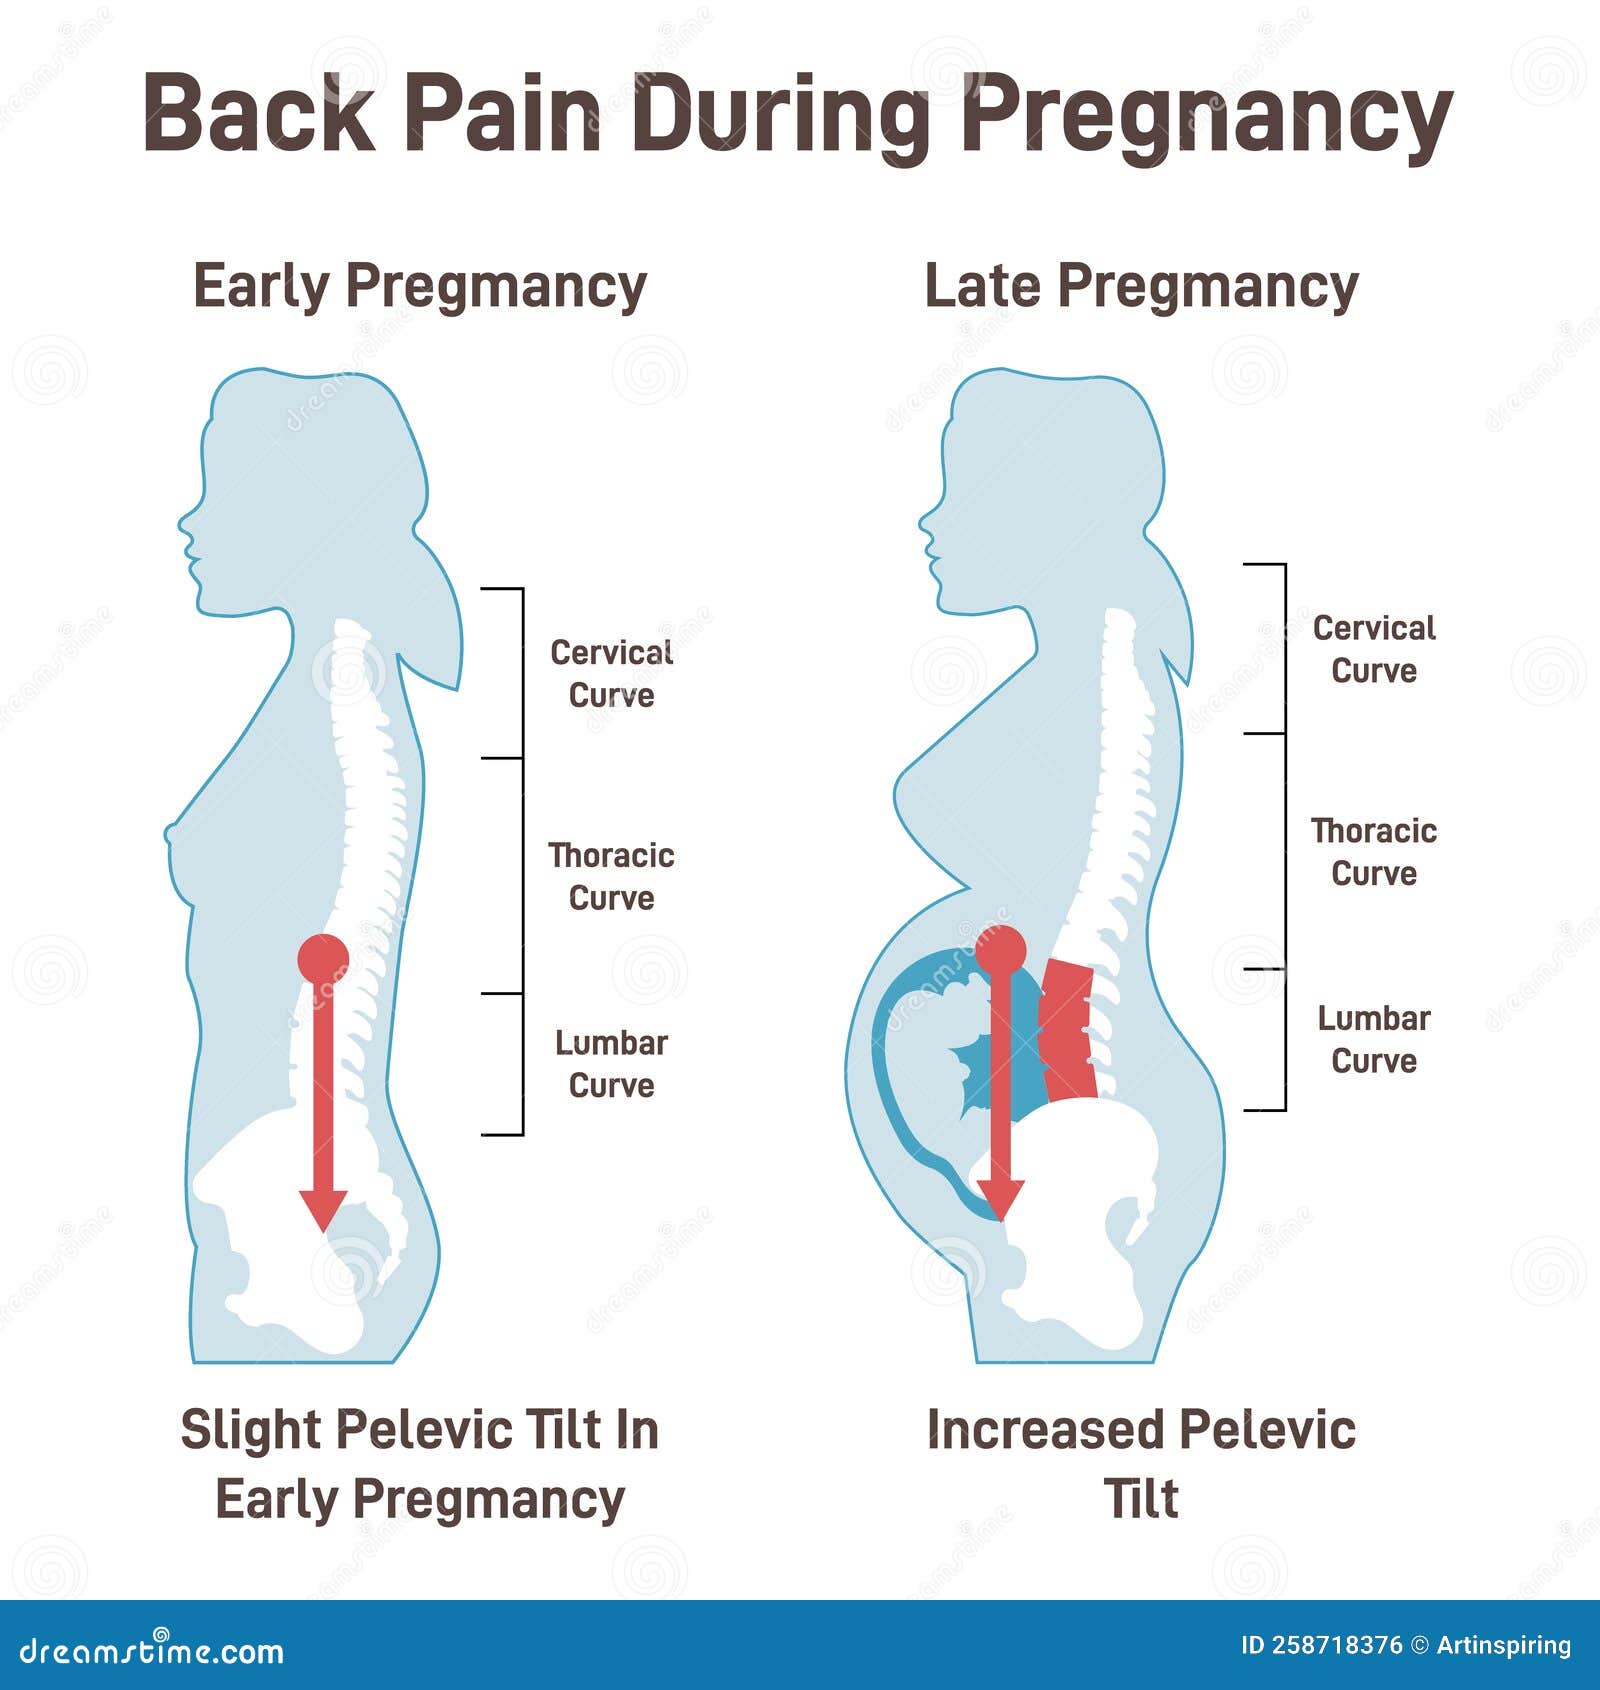

Low Back Pain In Pregnancy Loving Parents

Low Back Pain In Pregnancy Loving Parents

When Do Hips Start Hurting In Pregnancy Health Blog